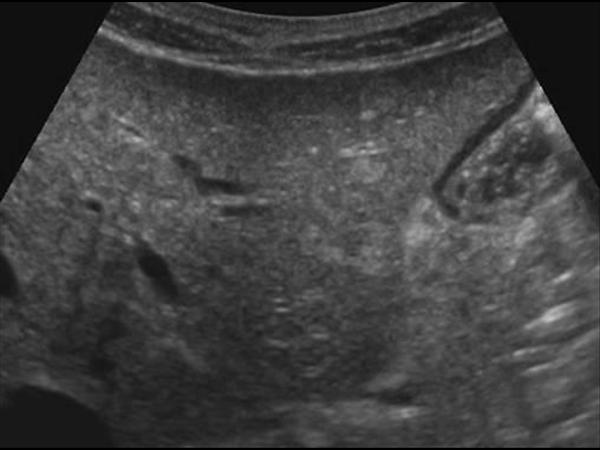

Gan nhiễm mỡ

Gan nhiễm mỡ - Ảnh 2

» Thông tin: Nữ giới – 56 tuổi.

» Lâm sàng: Kiểm tra sức khỏe.